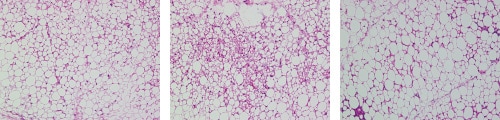

脂肪细胞由称为脂肪组织的脂肪滴组成,可分为两种类型:白色脂肪组织(WAT)和棕色脂肪组织(BAT)。每个白色脂肪组织的细胞都含有一个储存脂肪的大脂肪滴。棕色脂肪组织细胞含有大量的小液滴。这些细胞燃烧脂肪产生热量。

如果白色脂肪组织因肥胖而增大,脂肪细胞就会发生功能障碍,从而导致某些疾病的发生。

- 每个紧密间隔的脂肪细胞可以提取和计数使用混合细胞计数测量软件。